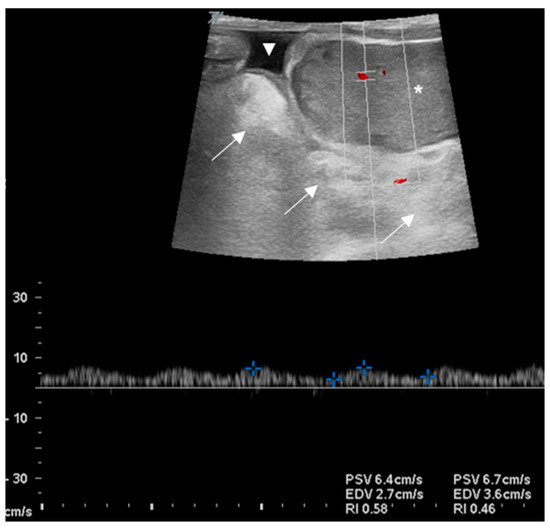

3.2. Clinical Cases

3.2.1. Case 1

3.2.2. Case 2

3.2.3. Case 3